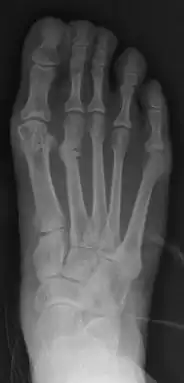

- For severe bunion deformity correction (Fig. 7)

- For recurrence correction after osteotomy procedure (Fig. 8)

Late deformity recurrence can happen after osteotomy (bone-breaking) procedures because osteotomy surgeries do not specifically stabilize first metatarsal bone.